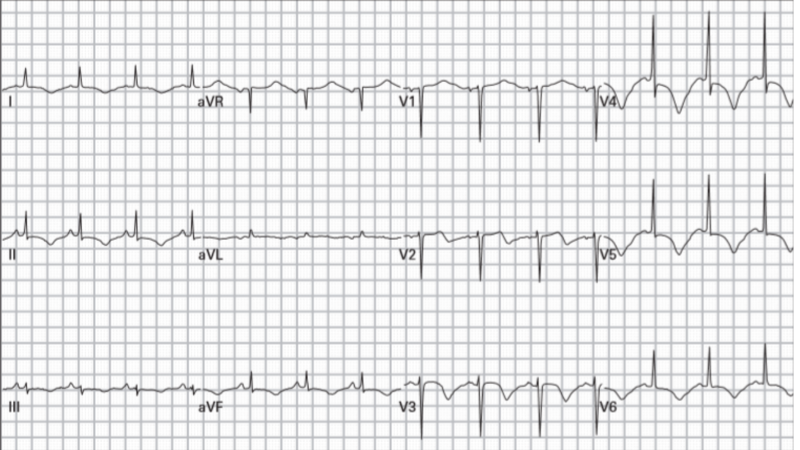

ECG’s na síncope: